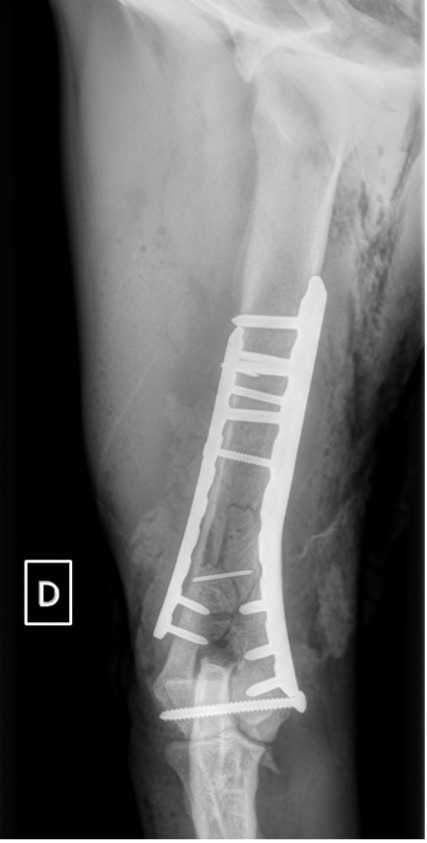

Notre préférence va vers le placement de deux plaques humérales : une médiale de la plus grande taille possible et l’autre latérale, généralement d’une taille inférieure à la première. Dans l’exemple 1 (chat européen), une plaque de 2 mm est utilisée médialement et une plaque de 1,5 mm latéralement. Dans l’exemple 2 (chien Malinois), une plaque de 3,5 mm est utilisée médialement et une plaque de 2,7 mm latéralement.

Exemple 2 :

Figure 6 : Post-Op 1 mois